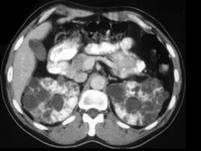

女,35岁,请根据CT图像,选择最可能作出诊断 ( )A、多囊肾B、单纯性肾囊肿C、多发性肾囊肿D、肾脓肿E、囊性肾癌

问题 女,35岁,请根据CT图像,选择最可能作出诊断 ( )

选项 A、多囊肾 B、单纯性肾囊肿 C、多发性肾囊肿 D、肾脓肿 E、囊性肾癌

答案 A